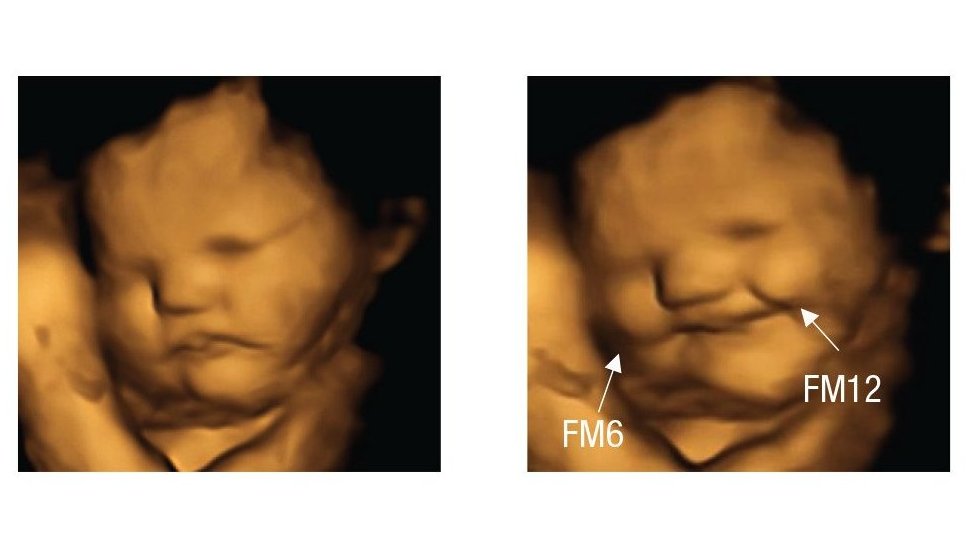

Así reaccionó este feto 20 minutos después de que su mamá comiera una capsula de zanahoria en polvo. (FETAL AND NEONATAL RESEARCH LAB, DURHAM UNIVERSITY)

En el estudio que publicaron en la revista Psychological Science, el grupo informó que 20 minutos después de que las madres tragaran las cápsulas las ecografías 4D mostraron que la mayoría de los fetos expuestos a la col parecían hacer una mueca.

Mientras tanto, los expuestos a las zanahorias parecían estar sonriendo.

Esta imagen del estudio FETAP (Preferencias de sabor fetal) muestra un feto haciendo muecas a la derecha, como reacción al sabor de la col rizada.